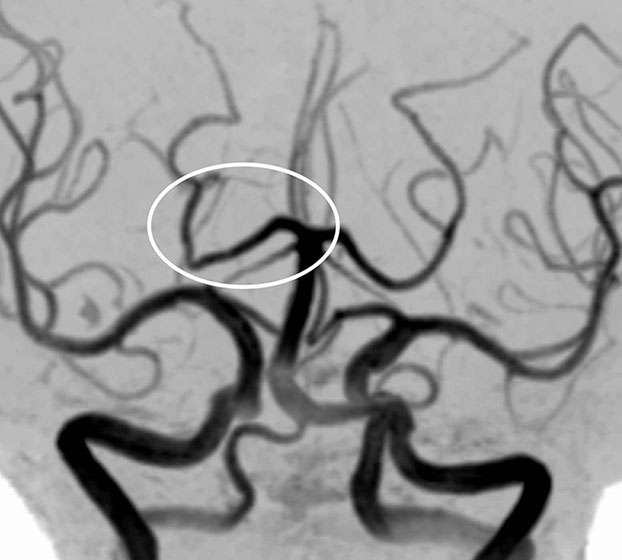

MRA検査(脳動脈の撮像)で見ても、

脳梗塞の原因となるような動脈硬化はなく、正常でした。

したがって、症状と画像所見から一過性全健忘と診断しました。